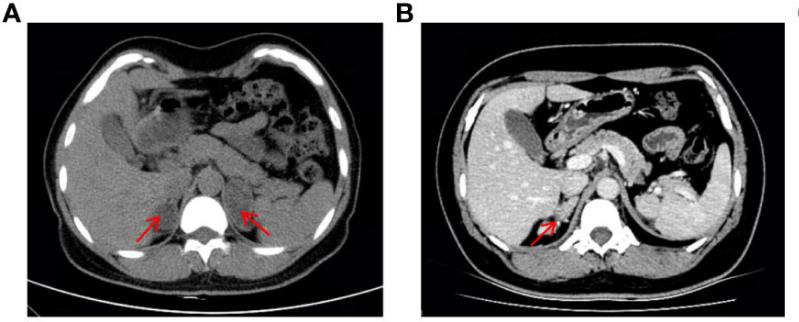

¸Ã»¼ÕßÊÇÒ»Ãû37ËêµÄÅ®ÐÔ£¨ºËÐÍΪ46£¬XX£©£¬Í¯Äêʱ±£´æÉú³¤¼ÓËÙ£¬ÇÒ»éºóһֱδÓÐÉí¡£2019ÄêÒòÒÉÕïË«²àÉöÉÏÏÙÖ×ÁöÈëÔº£¨Í¼1A£©£¬Ç°ºó¾ÙÐÐÁËÁ½´ÎÉöÉÏÏÙÇгýÊõ¡£2022Ä꣬»¼ÕßÓÉÓÚÔ¾­²»¹æÔò±»ÊÕÈëÄÚÉøÍ¸¿Æ£¬CTÏÔʾÓÒÉöÉÏÏÙÆ¤ÖÊÔöÉú¸´·¢£¨Í¼1B£©£¬Ìå¸ñ¼ì²éÏÔʾ¸Ã»¼Õ߯¤·ôÉ«ËØÀä¾²£¬Ã沿ÓÐðî´¯ºÍ÷×룬·ºÆðÄÐÐÔ»¯ÌåÕ÷£¬Éú»¯¼ì²éÌáÐѵͼØÐÔ¸ßѪѹ£¬¸ßÐÛѪ֢¡£¾ùÌáÐÑ11¦Â-OHDÕï¶Ï¡£

ͼ1  »¼Õ߸¹²¿CTÓ°Ïñ